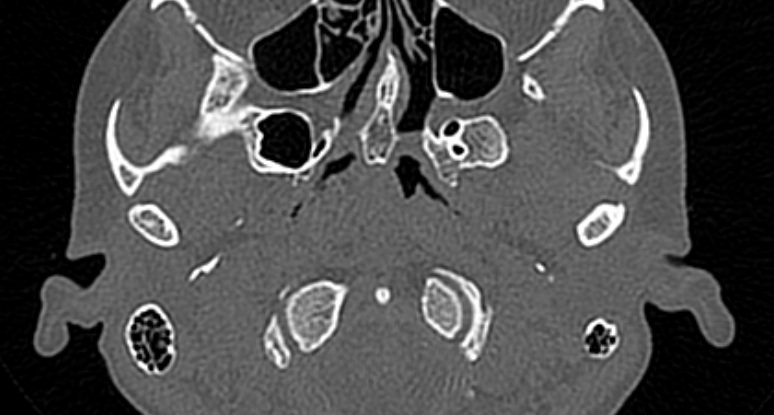

Наиболее точным и информативным методом диагностики костной патологии ВНЧС является мультиспиральная компьютерная томография. КТ относится к лучевым методам исследования, то есть для сканирования применяется рентгеновское излучение. В отличие от обычного рентгена томограф проводит одномоментно множество тончайших срезов исследуемой зоны, которые в дальнейшем проходят цифровую обработку. В результате получаются детальные снимки и трехмерные изображения области височно-нижнечелюстных суставов, которые позволяют проводить точную и достоверную диагностику.

Для оценки функции височно-нижнечелюстных суставов КТ-сканирование проводится в нескольких положениях: с открытым ртом и закрытым ртом. С помощью таких функциональных проб можно оценить положение суставной головки нижней челюсти при движениях нижней челюсти, выявить привычные вывихи и подвывихи суставов.

Компьютерная томография позволяет оценить состояние костных структур височно-нижнечелюстных суставов, так как рентгеновские лучи хорошо задерживаются костной тканью. Для повышения диагностических возможностей компьютерной томографии в ряде случаев дополнительно проводится контрастное усиление путем внутривенного введения йодсодержащего контрастного препарата. Эта методика применяется для улучшения визуализации мягких тканей, которые хуже видны при нативном исследовании.